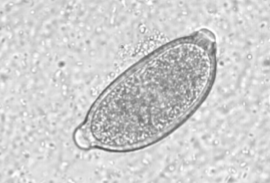

what techniques can you use to diagnose Aelurostrongylus abstrusus

fecal float and baermann technique (b is more reliable)